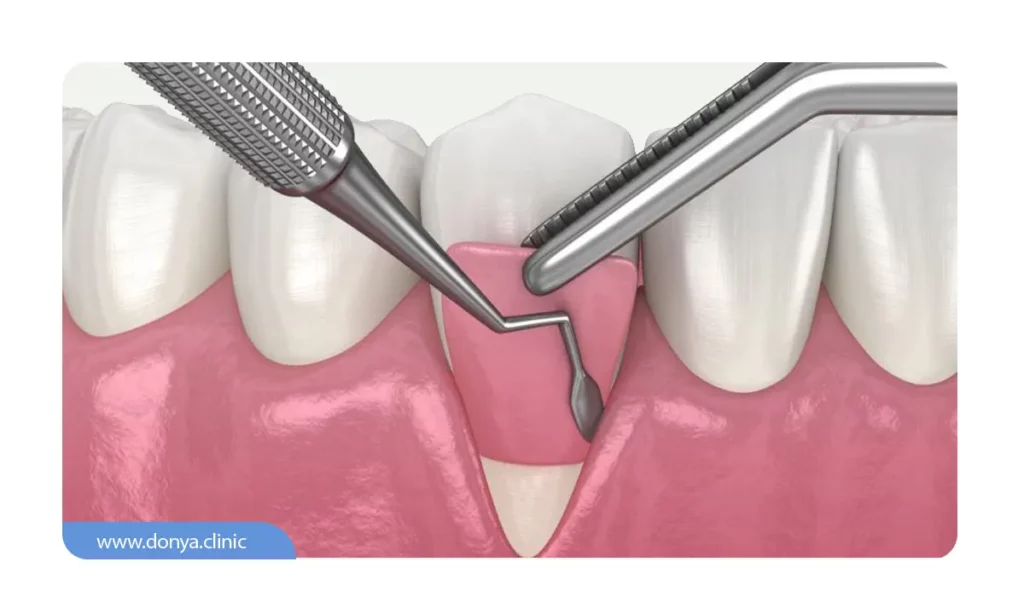

عمل جراحی فلپ لثه (Open flap scaling)

محل این عمل را یک متخصص پریودنتیست (متخصص لثه) یا یک دندانپزشک باتجربه انجام می دهند. در این روش بخشی از بافت لثه برش داده می شود و پس از از بین بردن باکتری ها و تمیز کردن کامل محل جراحی، لثه بخیه زده می شود. اینکار به از بین رفتن پاکت پریودنتال و کاهش احتمال آن کمک می کند.

مشابه روش جراحی فلپ لثه، در این روش هم برشی روی لثه زده می شود و بعد از پاکسازی زیر لثه، مواد احیا کننده (شامل غشاء، بافت گیوندی، پروتیئن و …) که باعث تحریک استخوان سازی و ترمیم لثه می شود استفاده می شود. پس از قرار دادن مواد احیا کننده، لثه محکم دوخته می شود.